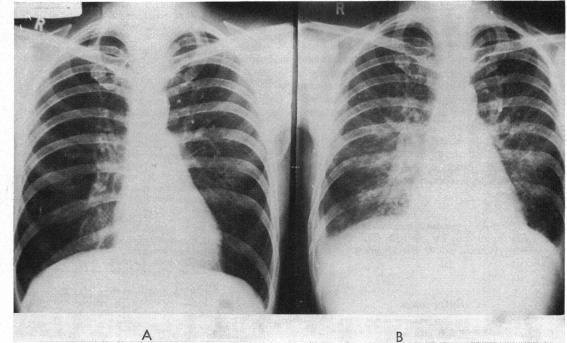

The clinical, laboratory, and necropsy findings in a patient with massive eosinophilia and fatal cardiac failure are reported. Necropsy revealed partial obliteration of the lumen of the left ventricle with dense white thrombus, and fibrous infiltration of the myocardium. An additional finding, not hitherto described in Löffler's endocarditis, was massive enlargement of the mesenteric lymph nodes.